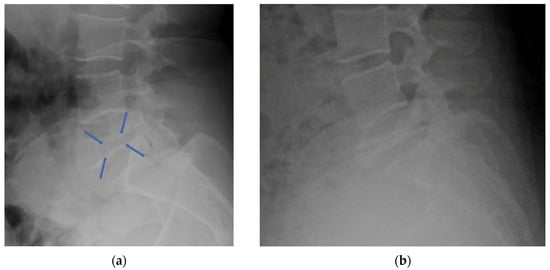

4.2.3. Plain Radiograph